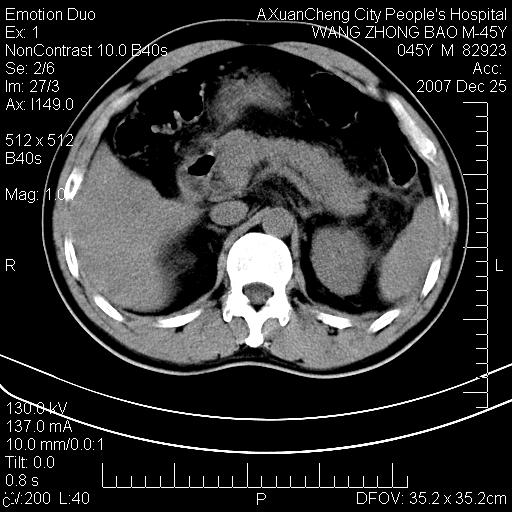

以下是引用qiuleiyu在2007-12-25 18:14:00的发言:[br]胰腺增大,周边渗出改变,肾前筋膜明显增厚,示少量积液.胆囊壁毛糙,周边少许渗出,胆总管壁厚,异常强化,然扩张不明显.结合病程急短;考虑;胆管炎,胆囊炎,胆源性胰腺炎可能大,请结合实验室检查及随访.

以下是引用lisihao在2007-12-25 14:23:00的发言:[br]急性水肿型胰腺炎[br]依据:1、胰腺弥漫性肿大,边缘稍毛糙;[br] 2、双侧肾周筋膜增厚,尤以左侧为甚(重要征象)[br] 3、双侧后胸膜增厚(刺激性炎症);[br] 4、结合病史,查血尿淀粉酶应该可以确诊。